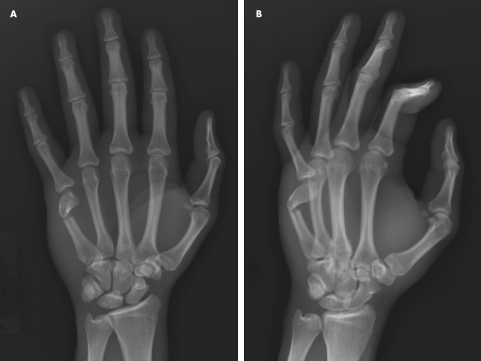

Looking at boxing, one would easily think that punches are not only easy but perfectly safe; at least for the attacker. Yet, people with knowledge of bare-knuckle fighting will know that the bones of the hand are infamously fragile, especially the metacarpals. When trying to punch a solid and irregular target, it is surprisingly easy to break those bones, most often the one connected to the little finger. This fracture is actually so commonly associated with the action of punching that the medical term “boxer’s fracture” is the modern clinical diagnosis.

One only needs to take a look at the recent advent of the Bare Knuckle Fighting Championship, or BKFC, an event which promotes a return to bare knuckle prize fights. At the first event of 2018, three out of ten fighters suffered broken hands. Despite some of the publicity surrounding it, the rules are not those of the London Prize Ring, and are in fact much closer to Queensberry’s, only without gloves and with very minimalist hand wraps. Because, while the knuckles are indeed bare, the wrist itself is still quite supported, which was unknown under LPR, and which plays a vital role in the way modern boxing is fought today.

All of this brings us back to our original question: why are straight punches seemingly absent from most of humanity’s martial past? As I observed earlier, the act of punching with the knuckles to the head is a very risky maneuver, especially for someone with little experience in doing so. Most fractures of the hand can be repaired today, though usually not without leaving stigmas, but in the world of pre-20th century medicine a hand fracture could easily cripple someone, and make them unable to earn a living. Even relatively simple injuries today can result in debilitating symptoms if not treated early. Once fractured, a boxer’s hands become increasingly prone to further breaks. Though once punches are mastered, they become a very useful weapon in boxing matches, and this is where I would like to make a point.